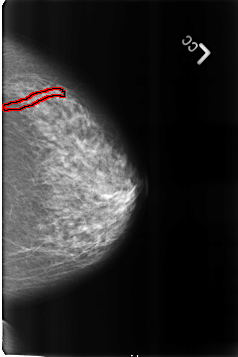

FILE: B_3254_1.LEFT_MLO.OVERLAY

TOTAL_ABNORMALITIES 1

ABNORMALITY 1

LESION_TYPE CALCIFICATION TYPE VASCULAR DISTRIBUTION N/A

ASSESSMENT 2

SUBTLETY 3

PATHOLOGY BENIGN_WITHOUT_CALLBACK

TOTAL_OUTLINES 1

BOUNDARY